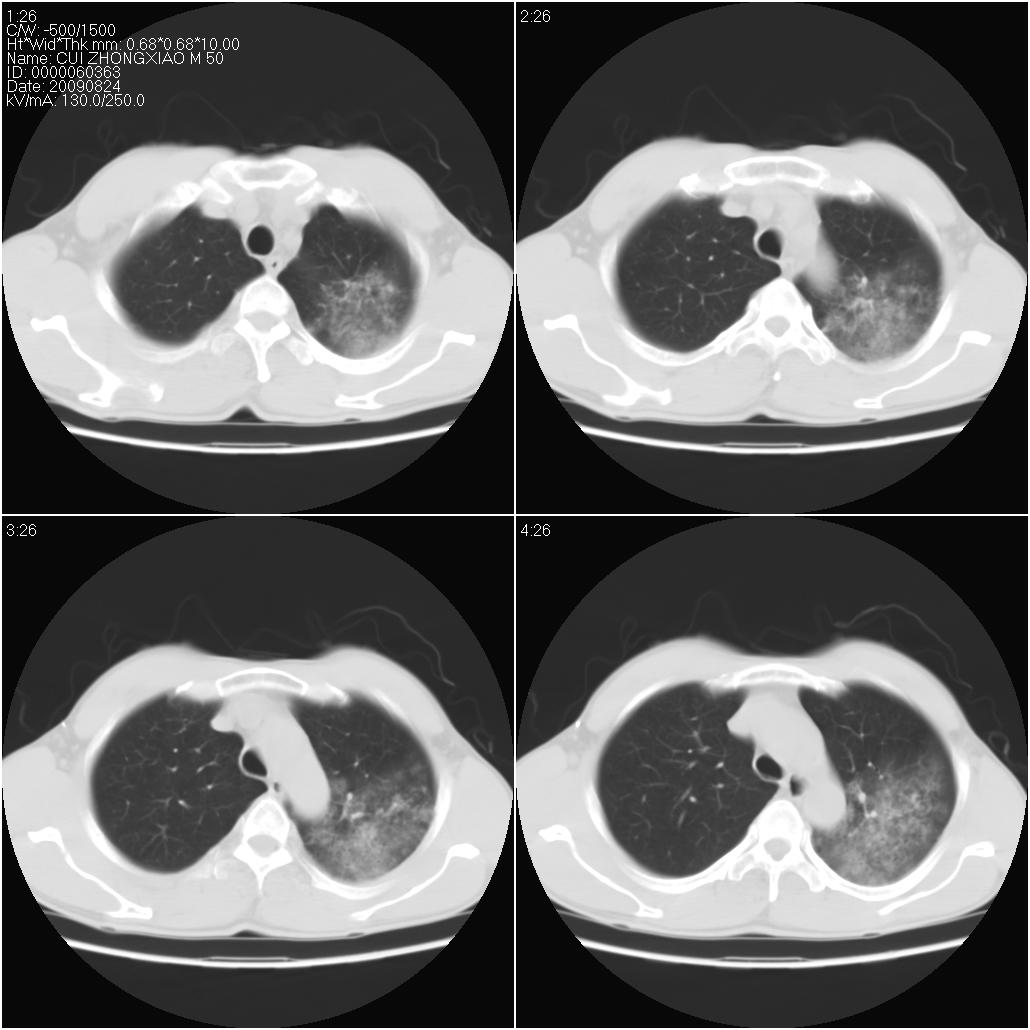

标题: CT21851:男性,50岁。间断性咳嗽半年。 [打印本页]

标题: CT21851:男性,50岁。间断性咳嗽半年。

磨玻璃样改变(左肺及右肺上叶前段),边缘模糊,考虑炎症,建议严格抗炎治疗后复查除外肺泡蛋白沉积症或肺泡出血(病人有咯血吗) 肺泡癌.

肝左叶肝内胆管扩张,进一步检查.

双肺磨玻璃征改变。。。支持楼上